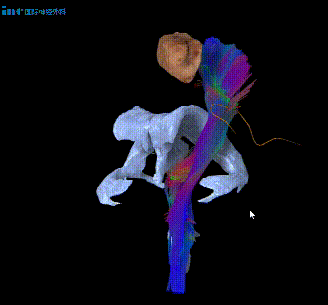

术前谈话时,巴教授表示已经通过特殊技术处理脑成像,以明确肿瘤位置及与运动神经纤维束的关系,如同绘制大脑中的地图一样。他强调,由于个体差异,术前充分了解这些信息对手术规划至关重要。“我们会竭尽所能(try the best)。”这句承诺,也给予了郑先生莫大的信心。顺利手术后,郑先生无需进ICU。